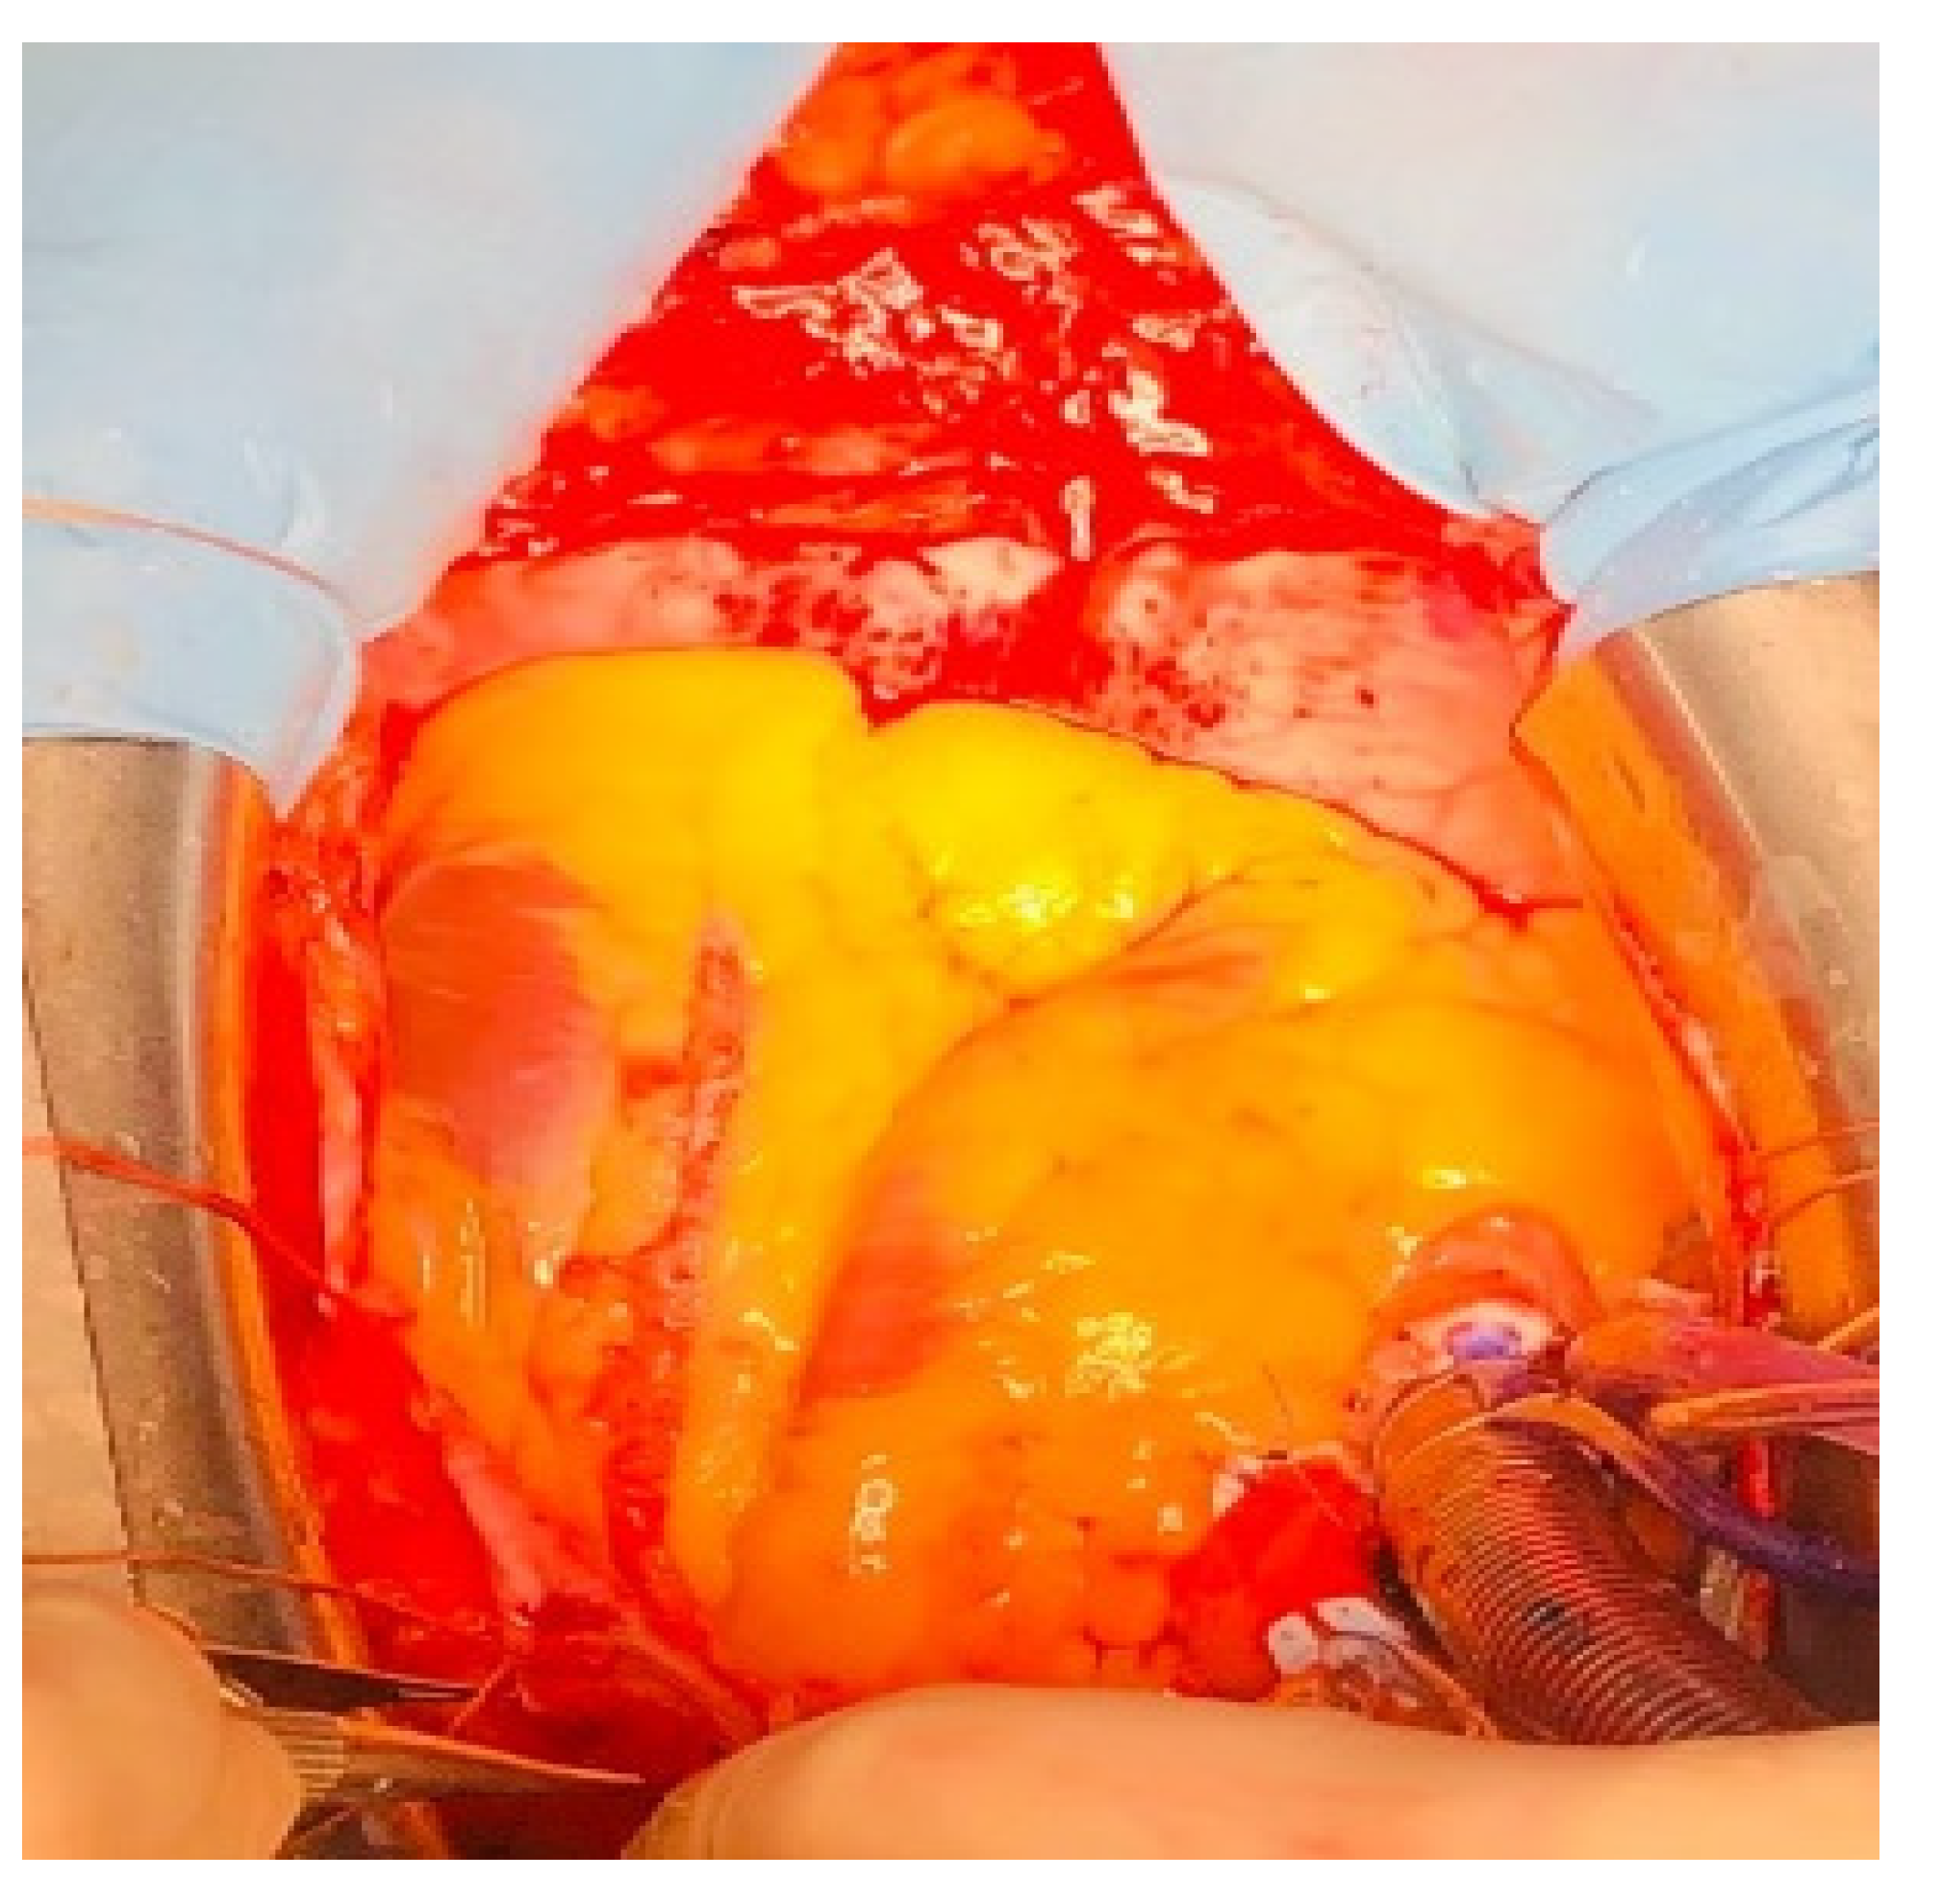

2. Case Report

Our Technique